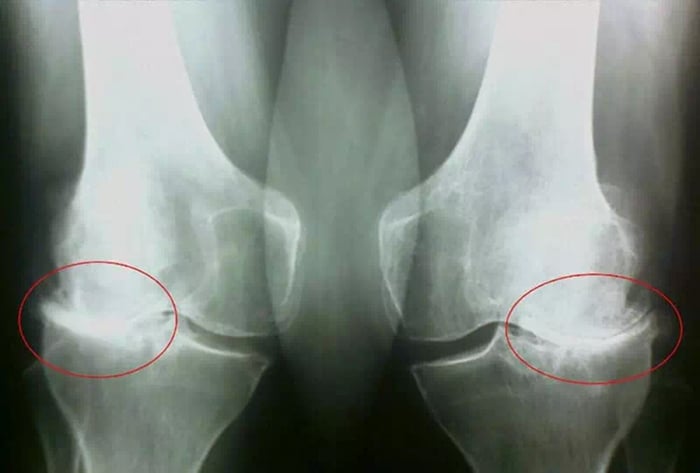

Началось всё неожиданно несколько лет назад. В самый обычный день, возвращаясь с тренировки и таща домой сумки из магазина, я вдруг почувствовала резкую, колющую боль в коленях. Сначала не придала значения — в спорте ведь всякое бывает: синяки, ушибы, растяжения. Всю жизнь я на лыжах, привыкла терпеть и идти дальше. Думала, как всегда, само пройдёт. Но в этот раз не прошло — наоборот, с каждым днём становилось только хуже.

Через пару месяцев колени начали болеть даже при самой обычной ходьбе. Для меня, лыжницы, которая привыкла к десяткам километров на трассе, это было шоком. Я пыталась объяснить себе, что это просто перегрузка суставов от постоянных нагрузок: тренировки, соревнования, а дома ещё заботы — то приготовить, то убрать, то тяжёлые пакеты притащить.

Я всё равно продолжала держаться — в спорте мы привыкли терпеть до конца. Но однажды утром я просто не смогла встать с кровати. Колени будто заклинило, боль была такая, что перехватывало дыхание. Сын подал обезболивающее, но и оно уже не помогло. Хорошо, что у соседей оказалась старая инвалидная коляска — неудобная, скрипучая, но хотя бы в ней я могла передвигаться. Так из мелкой неприятности всё очень быстро превратилось в страшную реальность.